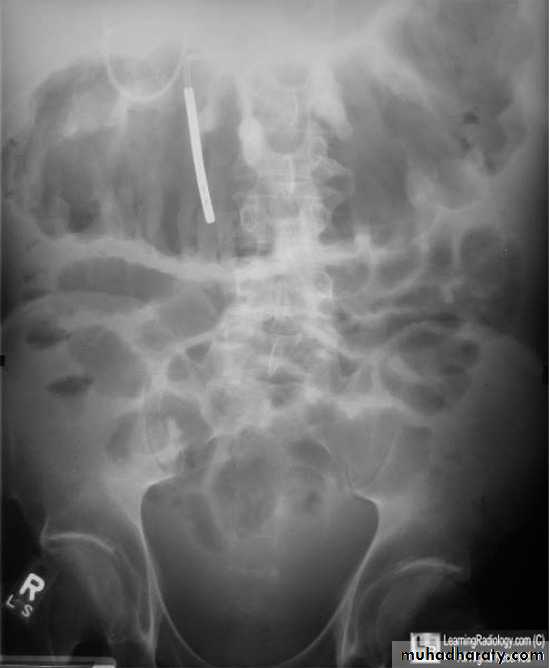

Bowel obstruction

Plain x ray SBOdilated loops with air fluid level in erect position

centrally placed

transverse lines (circular folds ) valvule convent's

Plain x ray LBO

dilated bowel with gasperipheral

haustra (not lines across bowel)

may have cut-off point